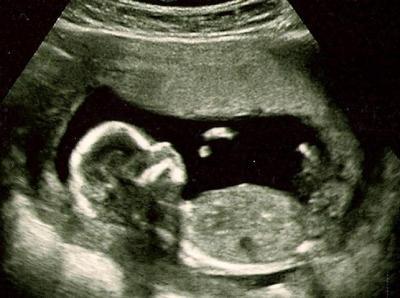

Zurück vom FA und total verliebt ♥. Es ist alles in Ordnung mit unserem Krümel. NFM war unauffällig, Organe alles in Ordnung. Sie tippt auf einen Jungen, aber will sich natürlich noch nicht festlegen. Ist jetzt 11,8 cm groß und wiegt 85 gr, bin lt. Ultraschall bei 13+0, eigentl. bei 13+4! Hach war das schön und das Herz haben wir schlagen hören. Hier noch 2 Bildchen!

Hier noch ein Foto von unserem Engel.

Bild zu